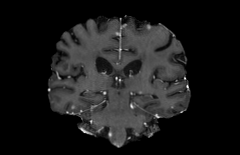

Objectives: This work aims to explore the impact of multicenter data heterogeneity on deep learning brain metastases (BM) autosegmentation performance, and assess the efficacy of an incremental transfer learning technique, namely learning without forgetting (LWF), to improve model generalizability without sharing raw data. Materials and methods: A total of six BM datasets from University Hospital Erlangen (UKER), University Hospital Zurich (USZ), Stanford, UCSF, NYU and BraTS Challenge 2023 on BM segmentation were used for this evaluation. First, the multicenter performance of a convolutional neural network (DeepMedic) for BM autosegmentation was established for exclusive single-center training and for training on pooled data, respectively. Subsequently bilateral collaboration was evaluated, where a UKER pretrained model is shared to another center for further training using transfer learning (TL) either with or without LWF. Results: For single-center training, average F1 scores of BM detection range from 0.625 (NYU) to 0.876 (UKER) on respective single-center test data. Mixed multicenter training notably improves F1 scores at Stanford and NYU, with negligible improvement at other centers. When the UKER pretrained model is applied to USZ, LWF achieves a higher average F1 score (0.839) than naive TL (0.570) and single-center training (0.688) on combined UKER and USZ test data. Naive TL improves sensitivity and contouring accuracy, but compromises precision. Conversely, LWF demonstrates commendable sensitivity, precision and contouring accuracy. When applied to Stanford, similar performance was observed. Conclusion: Data heterogeneity results in varying performance in BM autosegmentation, posing challenges to model generalizability. LWF is a promising approach to peer-to-peer privacy-preserving model training.